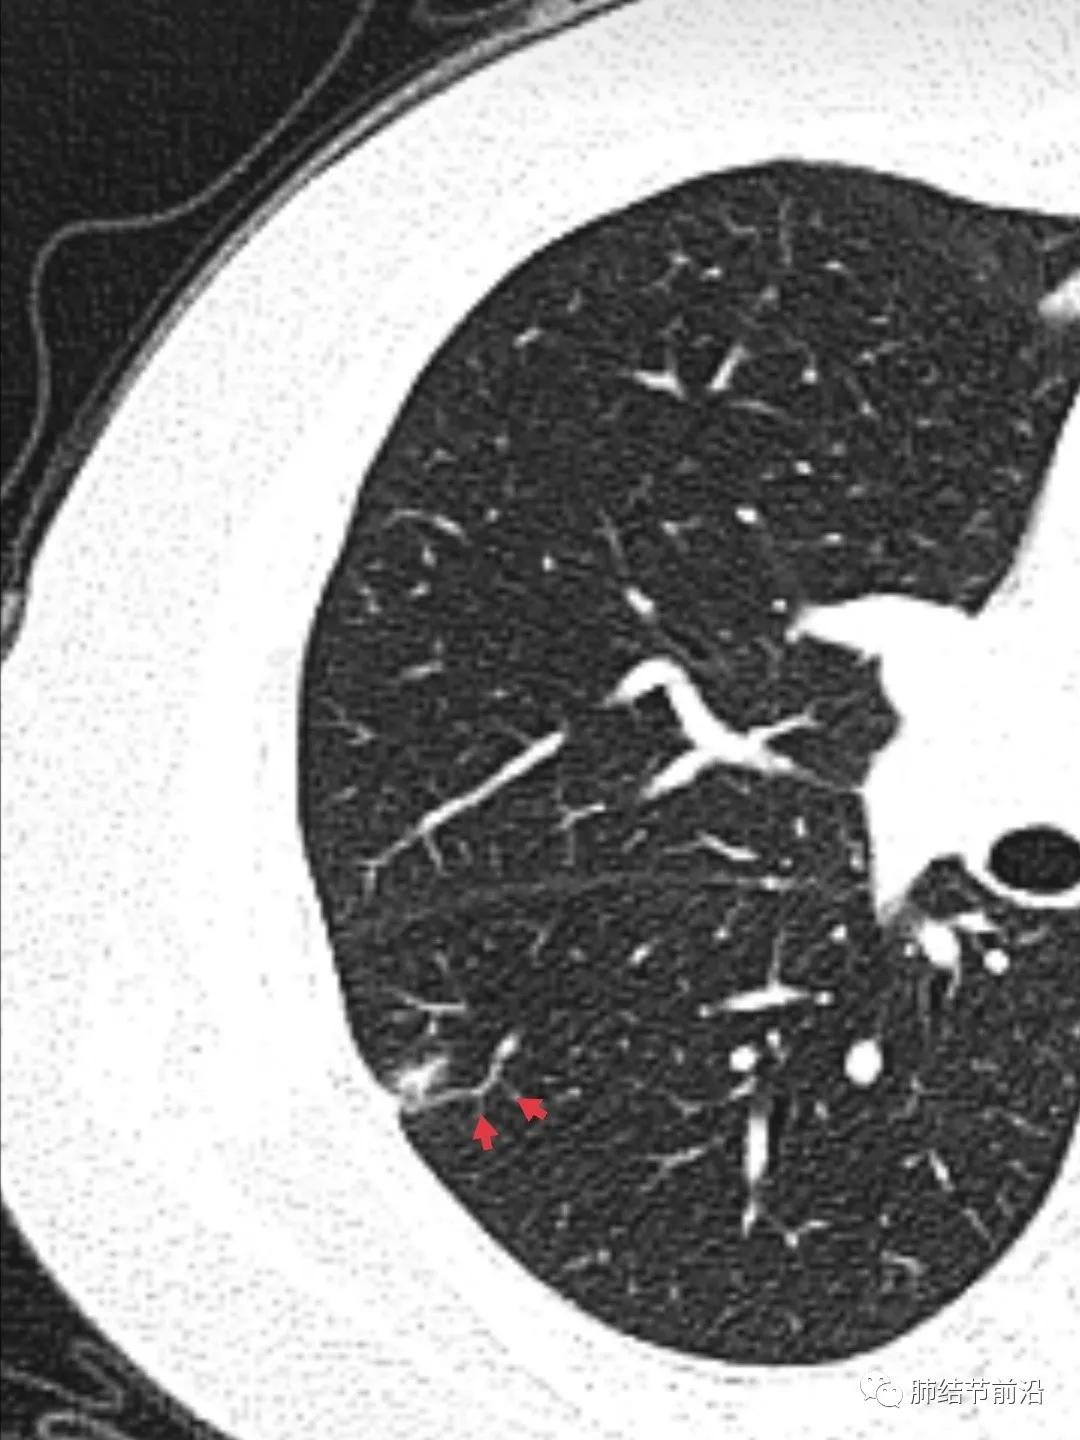

肿瘤组织需要氧供,新生血管是肿瘤的特征之一。传统的鉴别肺结节良恶性的标准之一就是血管集束征。然而在磨玻璃结节释放的血管生成因子并不强烈,新生血管不明显。则表现为诱导血管弯曲,出现明显有别于正常血管的弯曲现象,并向结节生长,称之为"血管弯"。这是肿瘤性磨玻璃/半实性结节很常见的特异性现象,出现这种表现,诊断磨玻璃/半实性结节为早期肺癌十拿九稳。“血管弯”名词引用自武汉市人民医院谭先华主任。

病例4

另外,“血管弯”也可以用于鉴别原位癌和微浸润腺癌。出现这种征象,说明肿瘤已经超过了原位腺癌,至少处于微浸润腺癌阶段,有今后生长加速的风险。